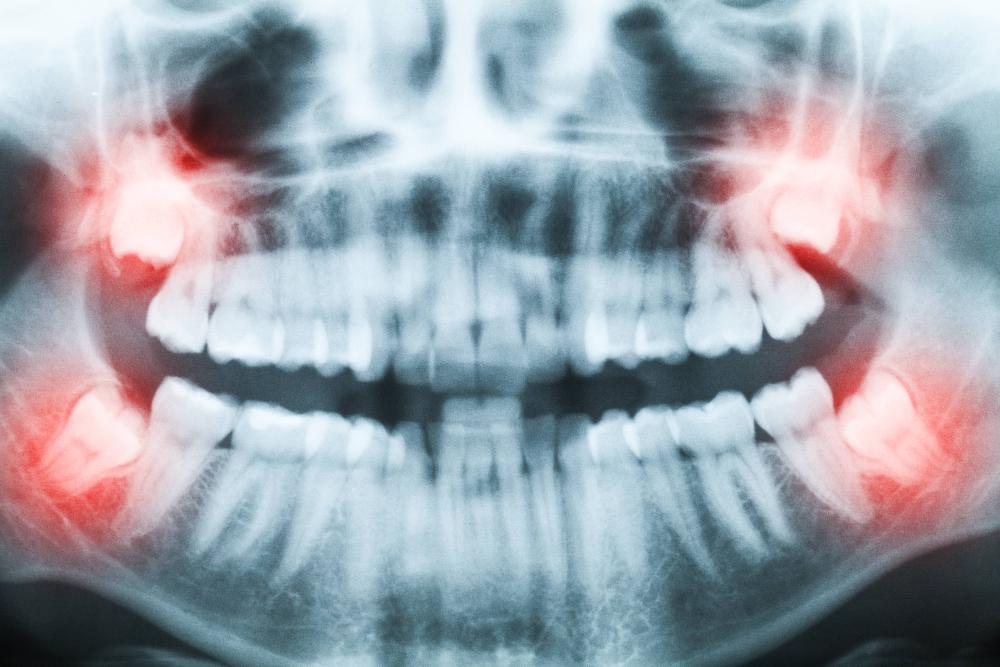

Periodic dental x-rays allow our dentist to see below the surfaces of your teeth. Decay can hide underneath your enamel or just below the gum line, making it impossible to detect with only a visual dental exam.

By using digital dental x-rays in our office, we obtain the highest resolution images available. This allows our dentist to accurately analyze the condition of your teeth as well as your periodontal and bone health.

X-rays are a dentist's most important diagnostic tool. Often, problems start inside your teeth or beneath the gum line. By the time the problem is visible to the naked eye, it can be painful and more difficult to treat. Using x-rays taken on a regular basis, we can catch problems early and treat them quickly and comfortably.